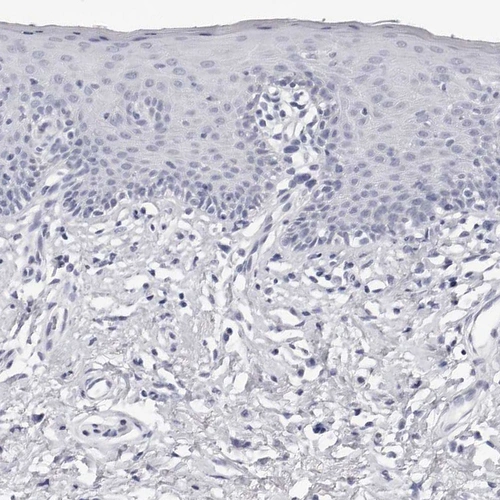

Immunohistochemistry analysis in human testis and liver tissues using HPA028615 antibody. Corresponding INSL3 RNA-seq data are presented for the same tissues.